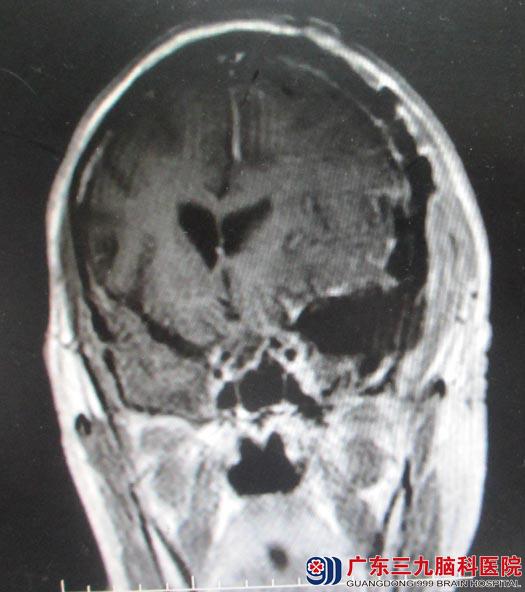

68岁的张大爷10年前因头部外伤损伤右眼,右眼视力失明 。两年前开始出现间断性的头痛, CT检查提示鞍区占位,朋友推荐他来到广东三九脑科医院综合神经外科进一步治疗。头颅MR检查发现:肿瘤大小约5.3cm×4.2cm×5.7cm,基底部位于左侧蝶骨嵴。

鲁明主任认为肿瘤基底部位于左侧蝶骨嵴,体积大,血供丰富,颈内动脉及其分支受肿瘤压迫移位,术中出血量可能较大。认真准备后后,在全麻下行左侧蝶骨嵴脑膜瘤切除术。术中取左侧扩大翼点入路,咬除蝶骨嵴,切除左侧颞极部分脑组织,分离部分外侧裂,见灰白色肿瘤组织,边界较清,从肿瘤边缘小心分离,肿瘤主要由左侧大脑中动脉分支供血,电凝离断肿瘤供血动脉,分块切除肿瘤,术中见左侧视神经被肿瘤压迫向下内侧移位,左侧大脑中动脉被肿瘤压迫推向背侧,与肿瘤粘连紧密,经小心分离,视神经及颈内动脉分支均保护完好,肿瘤镜下全切。术后,张大爷恢复良好,左眼视力基本同术前,四肢活动正常。病理结果示“过渡型脑膜瘤(WHO1级)”。

手术前